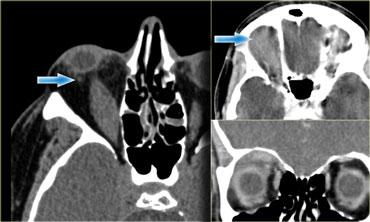

Áp xe quanh hốc mắt

Bên trái là hình ảnh CT không tiêm thuốc cản quang của một bệnh nhân có áp xe màng xương hoặc áp xe quanh hốc mắt rõ ràng do biến chứng của viêm xoang sàng.

Điểm cần lưu ý như sau:

Không cần chờ có viền ngấm thuốc ngoại vi mới chẩn đoán áp xe!

Ở các vị trí khác, chúng ta thường chờ có viền ngấm thuốc rõ ràng mới chẩn đoán áp xe, nếu không có thì gọi là viêm mô tế bào (phlegmone).

Điều trị là điều trị viêm xoang.Đây là hình ảnh MRI của một bé trai 11 tuổi, có biểu hiện kích thích mắt phải vào tối hôm trước và thức dậy với tình trạng lồi mắt.

Hình ảnh chuỗi xung T1W có tiêm thuốc tương phản từ kết hợp kỹ thuật xóa mỡ (fatsat) thể hiện rõ ràng áp xe quanh hốc mắt là nguyên nhân gây lồi mắt.

Lưu ý hình ảnh viêm xoang sàng.

Điểm quan trọng tiếp theo cần lưu ý là:

Ở trẻ em, cần hết sức thận trọng với sự lan rộng ra ngoài xoang!

Bất kỳ thay đổi nào bên ngoài xoang đều nên được chẩn đoán là áp xe.

Ở trẻ em, màng xương quanh hốc mắt có nhiều lỗ thông hơn và bệnh sẽ dễ dàng lan rộng.

Vì vậy, hãy mạnh dạn chẩn đoán áp xe ngay cả khi chỉ có những bất thường nhỏ.Áp xe quanh hốc mắt có thể dẫn đến huyết khối tĩnh mạch mắt trên và dưới.